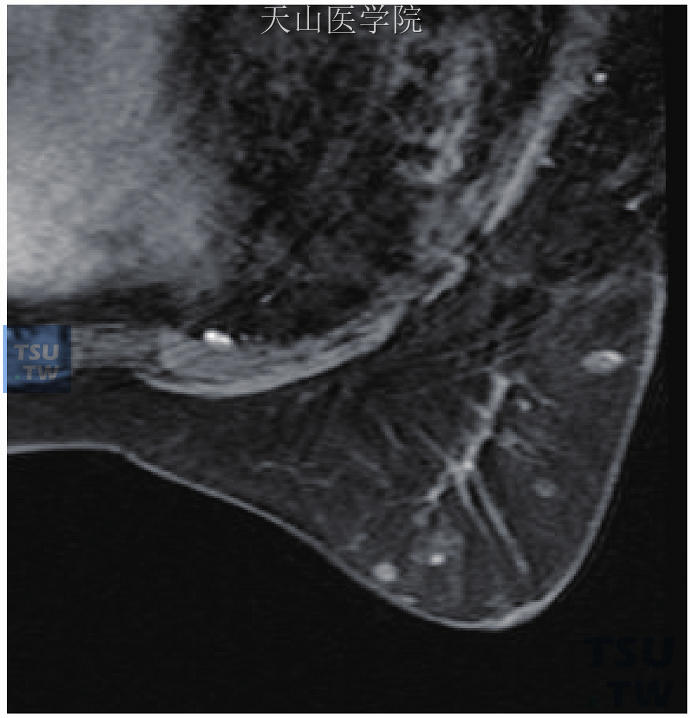

3(1)单纯囊肿:T1WI低信号(图11-48A),T2WI明显高信号(图11-48B),增强后无强化(图11-48C)。图11-48 囊肿(2)积乳囊肿(含脂肪):T1WI高信号(图11-49A),抑脂T2WI低信号(图11-49B),增强后无明显强化(图11-